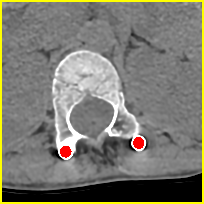

Simulation data. We generate 360,000 cases for training and 2,000 cases for testing based on clean CT images. We first resize CT images to a size of 416416 and use 640 projection angles and 641 rays for imaging geometry to simulate realistic metal artifacts (details are presented in Fig. 2).

Clinical data. We evaluate the proposed method using two clinical datasets. We refer them to DL and CL. DL represents the DeepLesion dataset [13] and CL is a clinical CT scan for a patient with metal rods and screws after spinal fusion. We randomly select 30 slices from DL and 10 slices from CL with more than 100 pixels above 3,000 HU and moderate or severe metal artifacts. The clinical images are resized and processed with the same geometry as the simulation data (see Fig. 2).